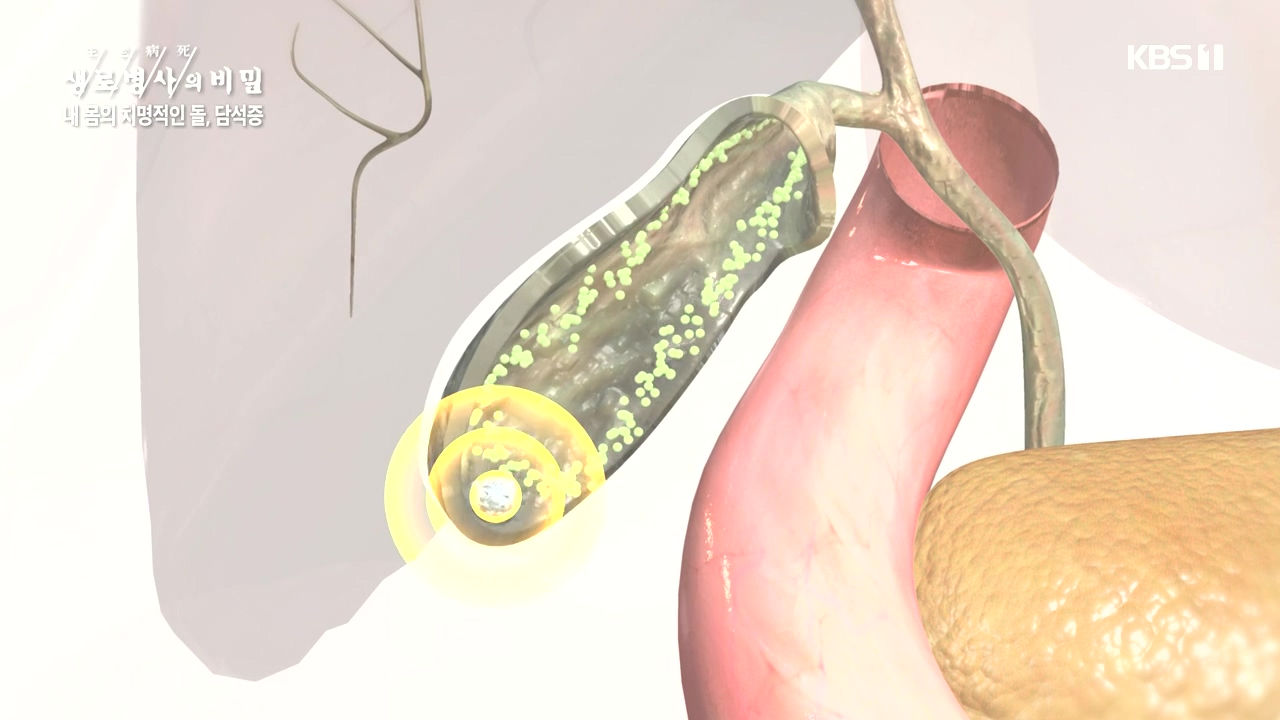

[박은철 기자] 담석증은 지방 소화를 돕는 담낭(쓸개)에 담즙이 굳어서 돌처럼 덩어리가 생기는 질환이다. 주로 쓸개주머니라 불리는 담낭 안이나...

다양한 합병증을 유발하는 몸속 시한폭탄, 담석증

내 몸의 치명적인 돌 담석증